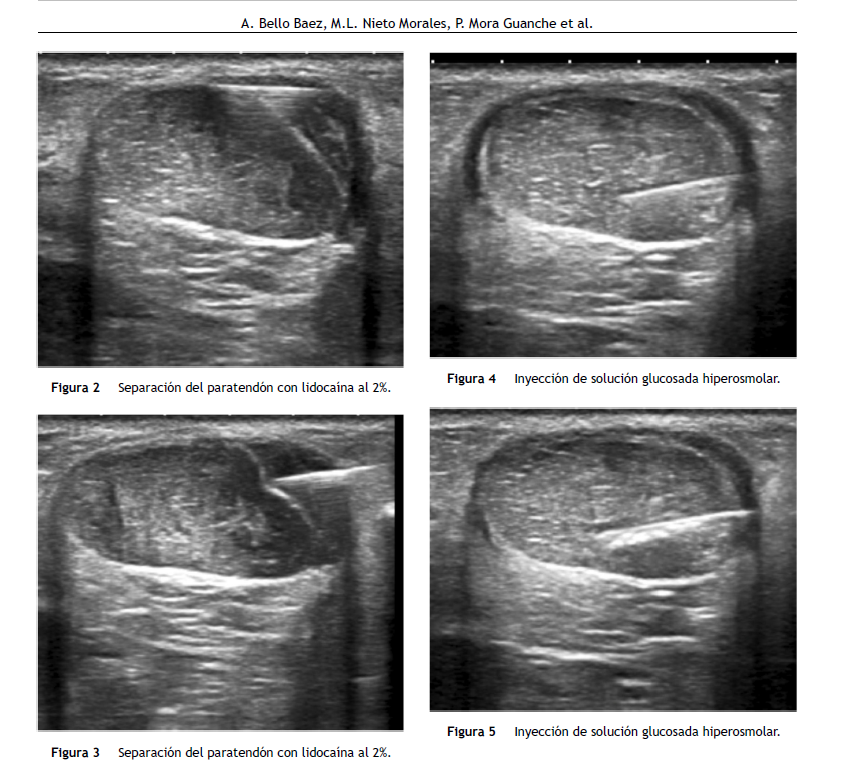

El tratamiento percutáneo de la tendinosis aquílea con proloterapia según el protocolo diseñado por el Dr. Bello implica el uso de tres técnicas: hidrodisección del paratendón con lidocaína, punción seca de los focos de degeneración tendinosa -tendinosis- y por último la administración de solución irritante hiperosmolar a base de suero glucosado y anestesia dentro de los focos de tendinosis. Es una técnica segura, barata y prácticamente indolora que da lugar a una reducción progresiva de los nuevos vasos sanguíneos que han entrado en el tendón debido a la degeneración de éste, y lo que es más importante, reduce el número de terminaciones nerviosas que acompañan a esos vasos (Vasa nervorum) y que se cree que son los responsables últimos de despertar dolor en dichos pacientes.  Esto provoca una disminución significativa de la percepción del dolor en reposo, con la actividad física diaria y durante el ejercicio moderado, que se mantienen con el tiempo.